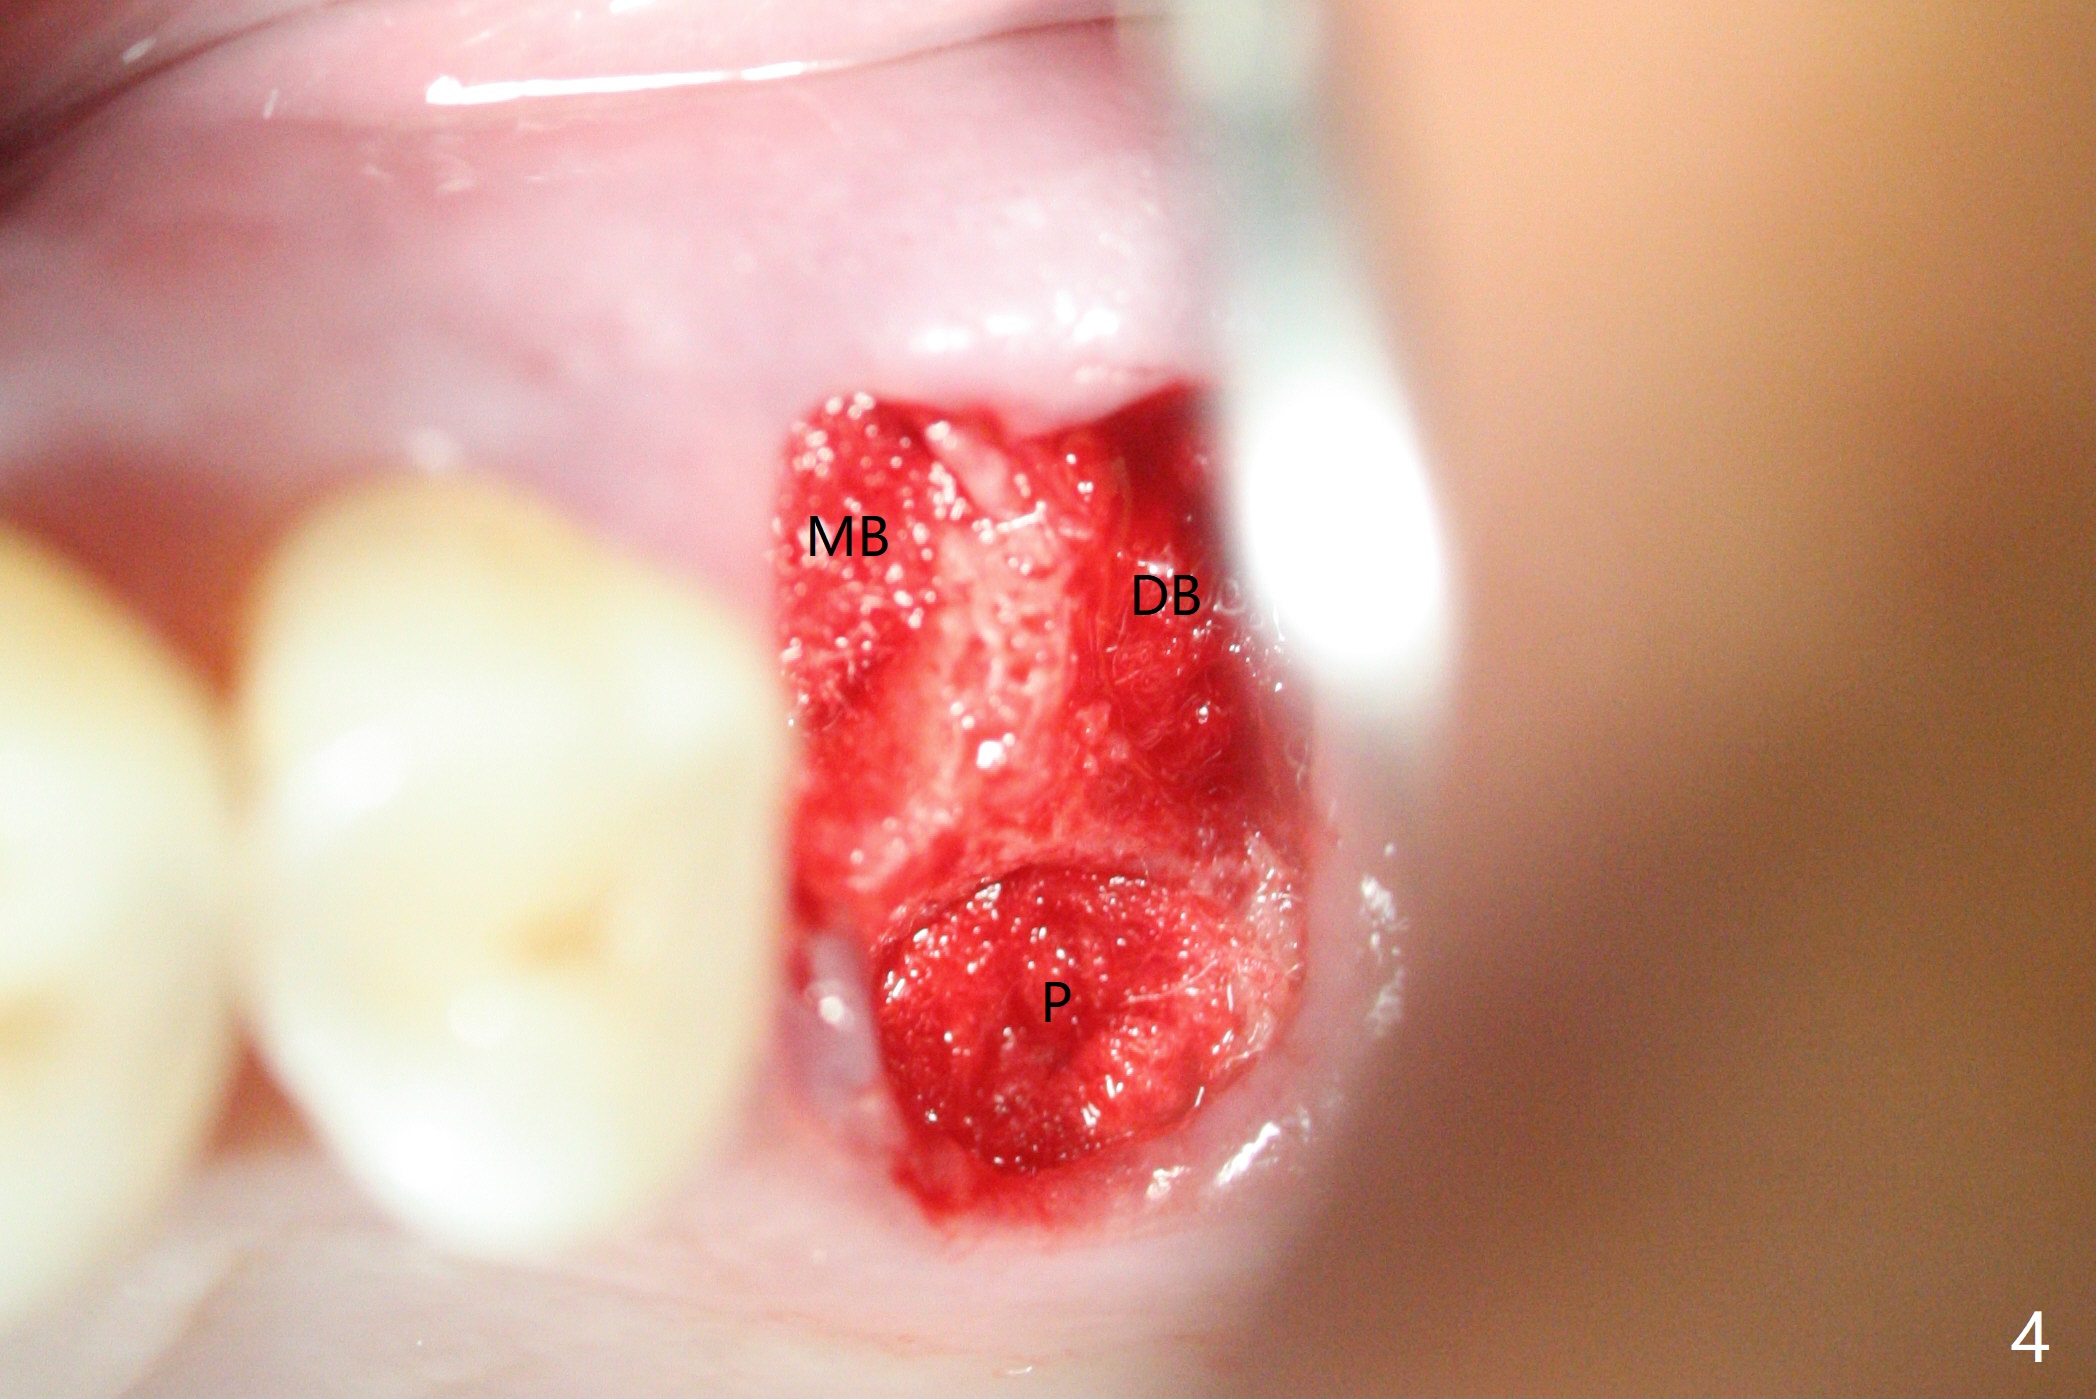

A 65-year-old man had crack tooth syndrome at #14 one month earlier (Fig.1). He shows up with crack and pain in an emergency manner (Fig.2 arrowheads). Preop CT confirms 4.5 mm bone height (Fig.3). Osteotomy will be initiated in the middle of the septum between 3 sockets (Fig.4). Depth of osteotomy is controlled with drill stoppers. After sequential osteotomy free hand, a 5x11 mm tap is used to break through the sinus floor (Fig.5) and sinus lift with Vanilla allograft. To prevent abutment screw loosening, a 5x11 mm tissue-level implant is placed; the distal thread is equicrestal (Fig.6 arrowhead). Following deeper placement of the implant (Fig.7 arrow) with a larger and longer abutment (as compared to that in Fig.6), the margin for an immediate provisional (Fig.9 white curved lines) is prepared in the coronal end of the implant (Fig.8 between arrowheads). With the tissue-level implant, the crown/implant ratio improves. Stress will be partially acting on the implant so that there is less likelihood of abutment screw loosening. The socket heals 1 month postop (Fig.10). The rough surface of the implant is exposed ~ 1 mm. With the margin modified and polished, the provisional returns to place with oral hygiene instruction. It is hoped that the gingiva will cover the exposed rough surface. The buccal rough surface remains exposed 5 months postop (Fig.11). The bone in sinus lift is mature 5 months postop (Fig.12,13). The first 1-2 implant threads are expected to be filled with mature bone in the near future (*). Since the abutment seems long enough for retention, temp bond is used for cementation (Fig.14). Water pik is being applied.